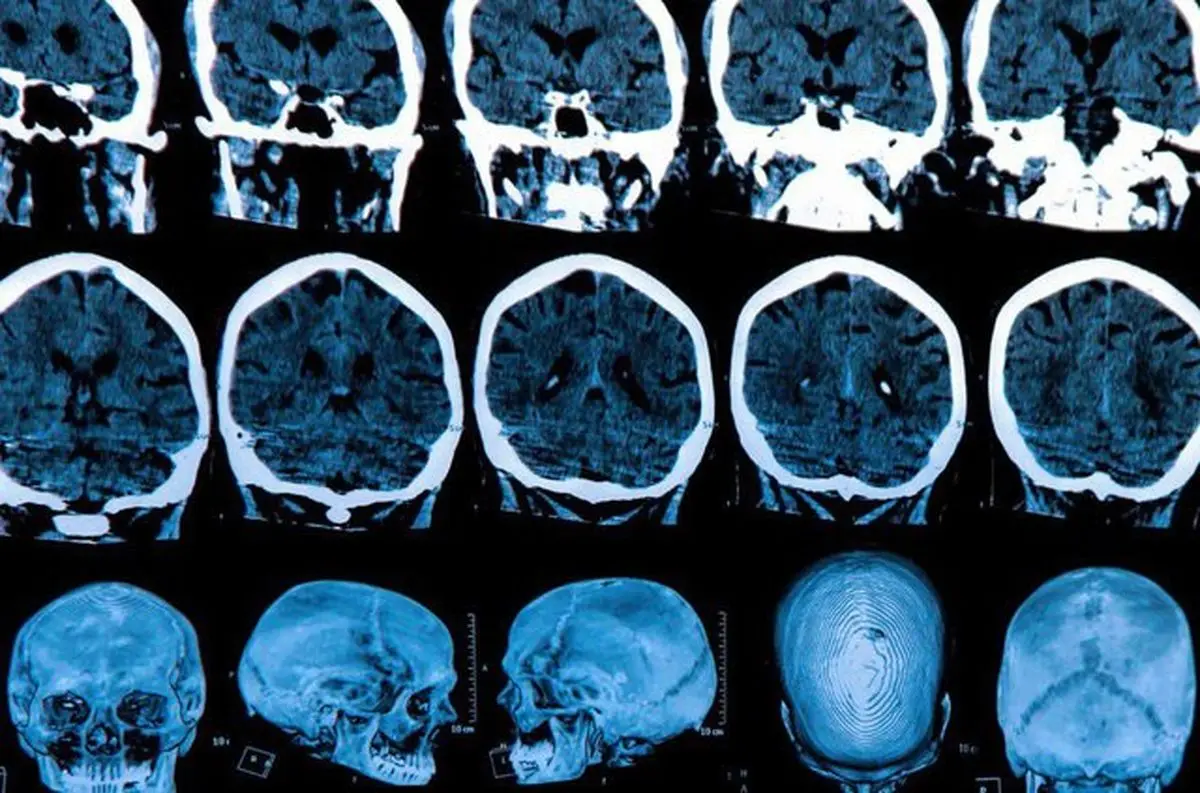

توالیهای تکراری RNA های خاموشگر یافت شده در آسیب شناسی هانتیگتون بسیار شبیه به ملکولهای RNA های خاموشگر کشف شده در مطالعه پیشین تیم بودند. بنابراین گام بعدی آزمایش این بود که آیا این ملکولهای خاص هنگامی که از طریق نانوذرات به بدن موشها منتقل شدند، واقعا برای کشتن سلولهای سرطانی کار می کردند یا خیر. نتیجه باورنکردنی بود، رشد تومور به طور قابل توجهی در انواع مختلف سلولهای سرطانی، از جمله سرطان تخمدان، پستان، پروستات، کبد، مغز، ریه، پوست و سلولهای سرطانی روده بزرگ، کاهش یافت .